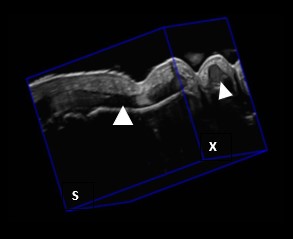

NovaSonix Healthcare is transforming musculoskeletal (MSK) imaging with MSKNovaVue™, an attachment that turns any standard ultrasound machine into a real‑time 3‑dimensional scanner. Designed to work with any commercially available ultrasound machine, MSKNovaVue™ automatically captures full 3D images in seconds, while on‑board AI algorithms quantify disease biomarkers such as cartilage thickness and joint inflammation. By capturing true volumetric and dynamic data, MSKNovaVue™ delivers MRI‑like insight at a fraction of the cost and without the long wait times that plague today’s patients and clinicians.

3DUS allows for improved:

- Quantification of inflammation (e.g., synovitis)

- Detection of disease extent (e.g., arthritis)

- Detection of injury/trauma (e.g., tears, cysts, edema)